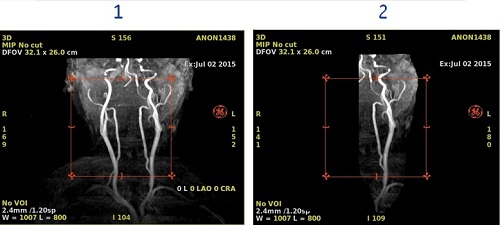

Figure 1. Image with and without cut applied

Table 1. Image legend

NumberDescription

1MIP image with no cut applied.

2MIP image with one artery cut.